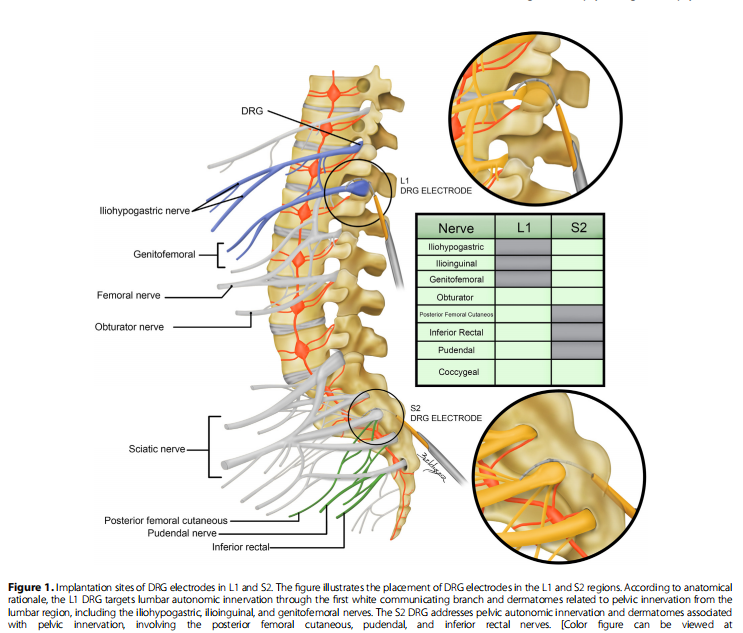

电极放置术中影像

背根神经节刺激(DRG-S)手术分为两个阶段,针对双侧L1和S2背根神经节。第一阶段为测试,设置传统参数(脉冲宽度200-300μs,频率20 Hz,振幅70%-80%的痛觉阈值,通常在0.2-0.8 mA之间),并于第4天和第7天评估。若患者疼痛改善≥50%(VAS评分),则进入第二阶段,即永久植入DRG-S电极和植入式脉冲发生器于臀部。术后12个月随访,调整DRG参数以实现最佳效果。